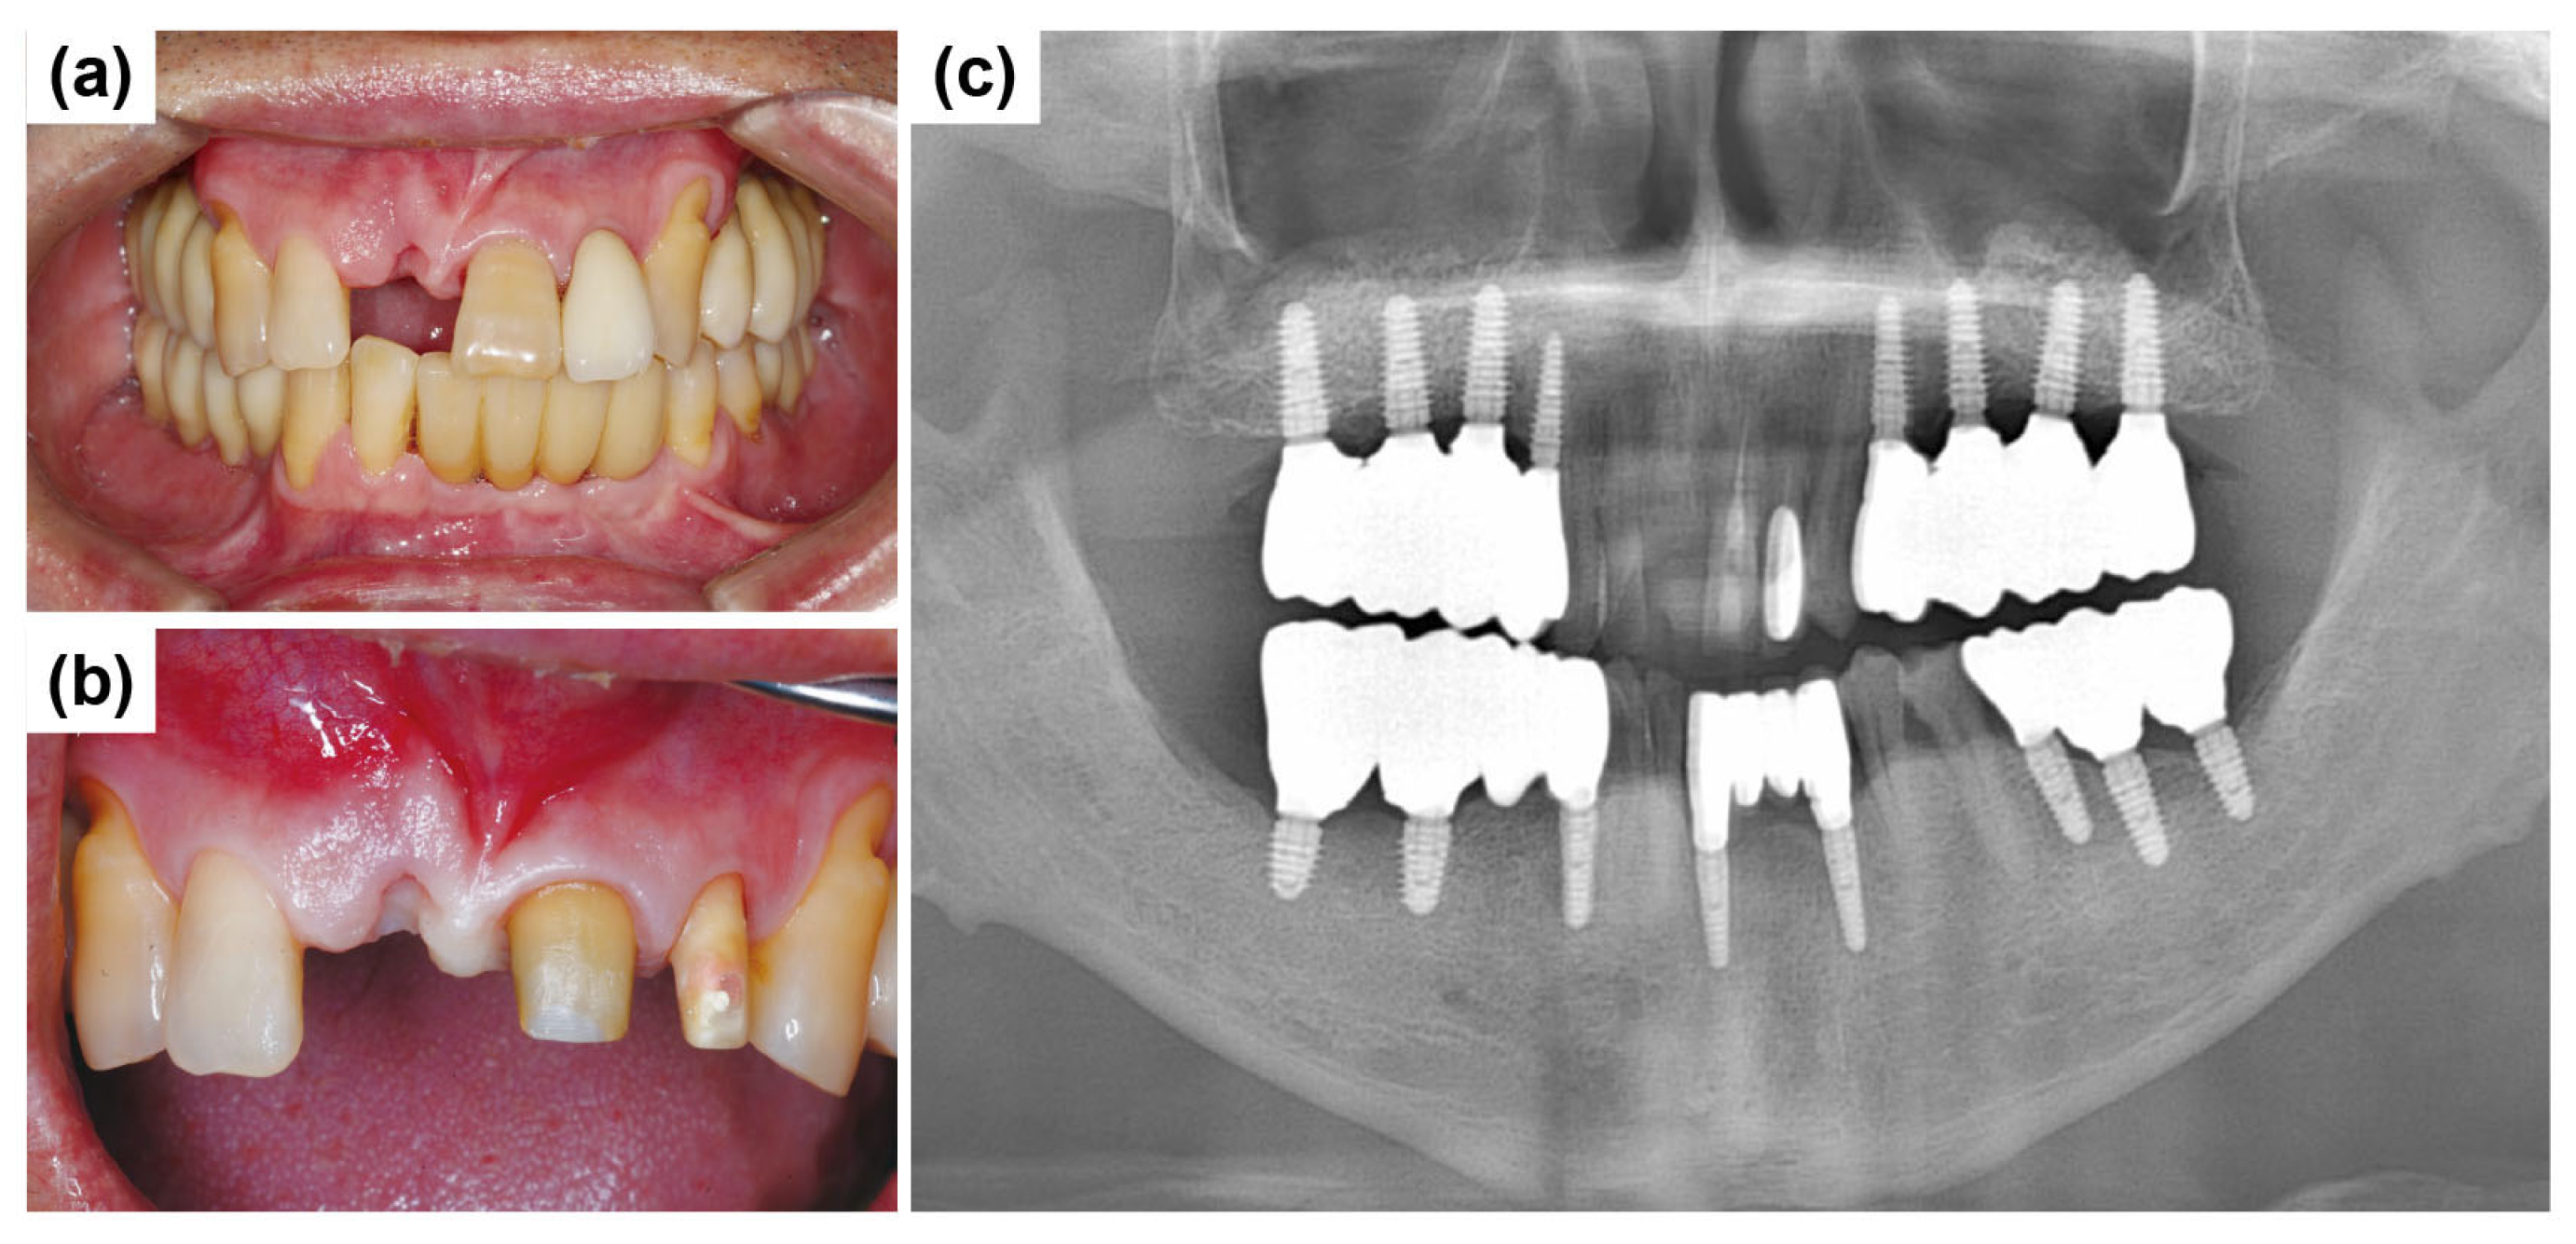

A 50-year-old male patient reported to the Mir Dental Hospital at Daegu without tooth #11. The patient stated that tooth #11 was lost to periodontal disease approximately five months before his visit. He was a non-smoker and had no significant systemic conditions. Intraoral examination confirmed the extraction site of tooth #11 (Figure 12a). Clinical inspection revealed severe alveolar bone loss around the apex of the missing tooth #11. The patient expressed concerns regarding the color and morphology of teeth #21 and #22, requesting esthetic improvements. Consequently, the treatment plan was expanded to include new prosthetic restorations for teeth #21 and #22 (Figure 12b). Figure 12c shows the initial panoramic radiograph, illustrating the patient’s overall periodontal condition and alveolar bone status.

Figure 12.

Preoperative clinical and radiographic evaluation. (a) Missing tooth #11 at the initial visit. (b) Preparation of teeth #21 and #22 for fabricating the new restoration. (c) Initial panoramic radiograph shows overall periodontal condition and alveolar bone status.